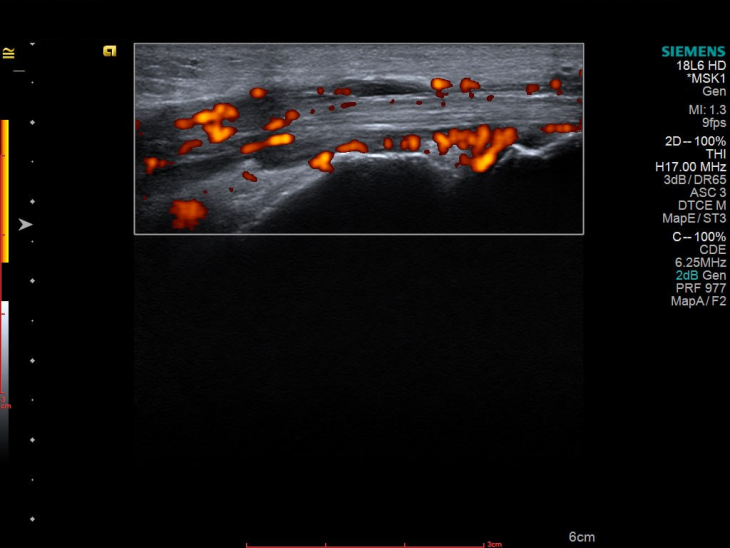

УЗД 3-го пальця продемонструвало не просто запалення, а його розгорнуту, системну картину, а саме виражений випіт у всіх суглобах пальця, потовщені м’які тканини та ознаки ентезиту сухожилків згиначів. Такий комплекс змін вже не вписувався в ізольований подагричний напад.

Картина доповнилася після обстеження гомілковостопного суглоба, бо було виявлено активний теносиновіт.

І що важливо — при всій цій запальній активності УЗД не показало жодної типової для подагри ознаки: ні подвійного контуру, ні тофусів.

Саме тому УЗД у цій історії стало не просто допоміжним методом, а інструментом, який фактично «перевернув сюжет». УЗД дозволило побачити системний характер запалення там, де клініка ще залишала сумніви.

УЗД, у свою чергу, вміє знаходити те, що клініка може пропустити — навіть субклінічні теносиновіти й ентезити. А саме такі деталі часто вирішують усе: і діагноз, і подальшу долю терапії.